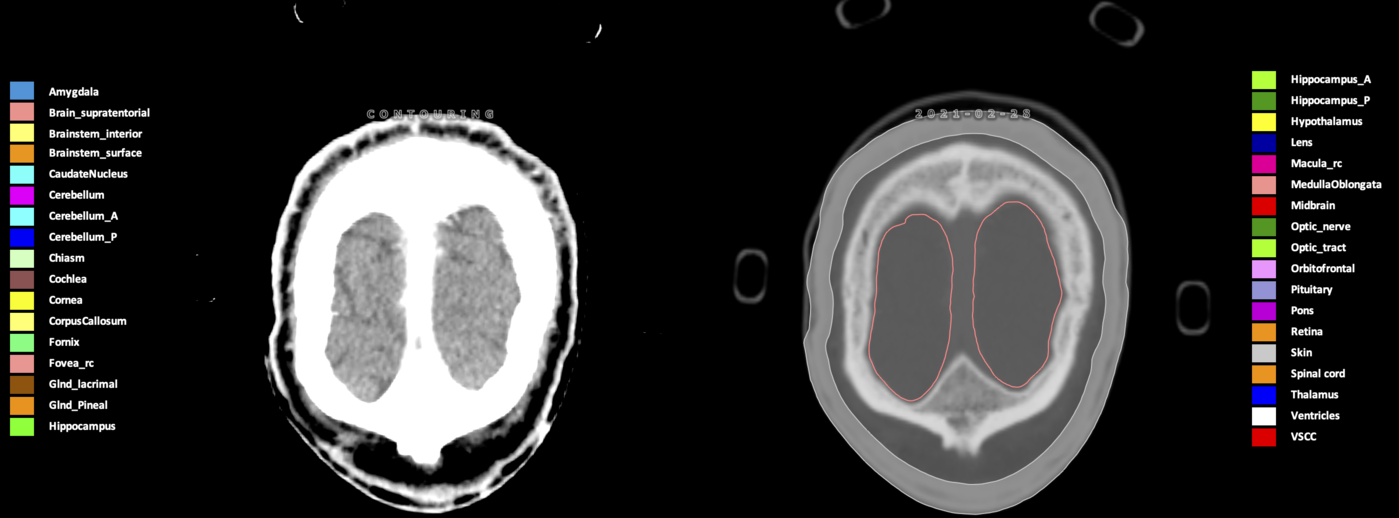

Included are all OARs known to be relevant for radiation-induced toxicity in neuro-oncology: brain, brainstem (midbrain, pons, medulla oblongata), chiasm, cerebellum (anterior & posterior), cochlea, cornea, hippocampus (anterior & posterior), hypothalamus, lens, lacrimal gland, optic nerve, pituitary, skin, and vestibular & semicircular canals. To further facilitate research on cognition, vision and radiological changes after irradiation of the brain, potential clinically-relevant OARs are included: amygdala, caudate nucleus, cerebellum (anterior & posterior), corpus callosum, fornix, macula, optic tract, orbitofrontal cortex, periventricular space (PVS), pineal gland, and thalamus.

Three-dimensional delineation of the 25 consensus OARs for neuro-oncology are shown on CT (WW/WL 120/40, 3000/600), 3T MR images, (T1Gd, T2FLAIR 1mm) and 7T MR (MP2RAGE 0.7 mm). All are presented in transversal, sagittal and coronal view.